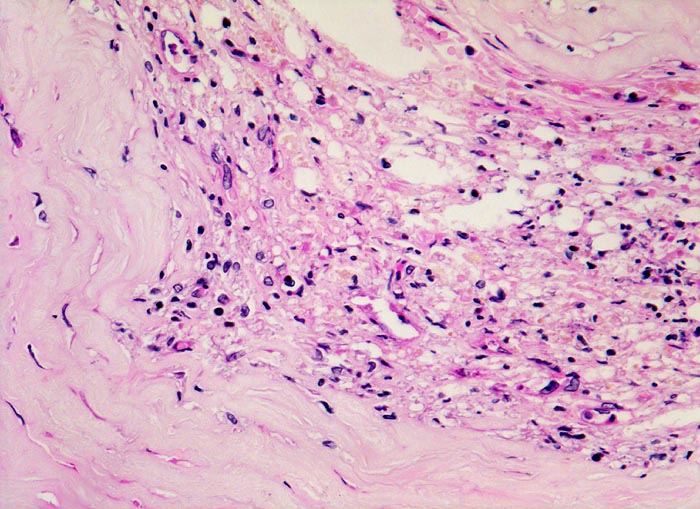

Makroskopisch sind Thromben am besten auf Querschnitten in 3 bis 5mm Abständen durch die Koronargefässe darstellbar. Thromben, die zum Tod des Patienten geführt haben, erkennt man meist makroskopisch. Mikroskopisch findet sich ein Kontinuitätsunterbruch in einer entzündlich veränderten fibrösen Deckplatte über einem Atherom. Dadurch gerät der lipidreiche Kern des Atheroms in Kontakt mit dem luminalen Blutstrom und dies führt zur Ausbildung eines Plättchen-Fibrin Thrombus und zur Einblutung in das Atherom. Meist zeigt der Thrombus Zeichen der beginnenden Organisation. Histologisch ist bei einer Ruptur die denudierte Endotheloberfläche von einem luminalen Thrombus bedeckt.

• Atherom mit fibröser Deckplatte.

• Organisierender geschichteter Abscheidungsthrombus über Defekt in der fibrösen Deckplatte. Der Thrombus enthält zusätzlich Atherombestandteile (Cholesterinkristalle und nekrotischer Detritus).